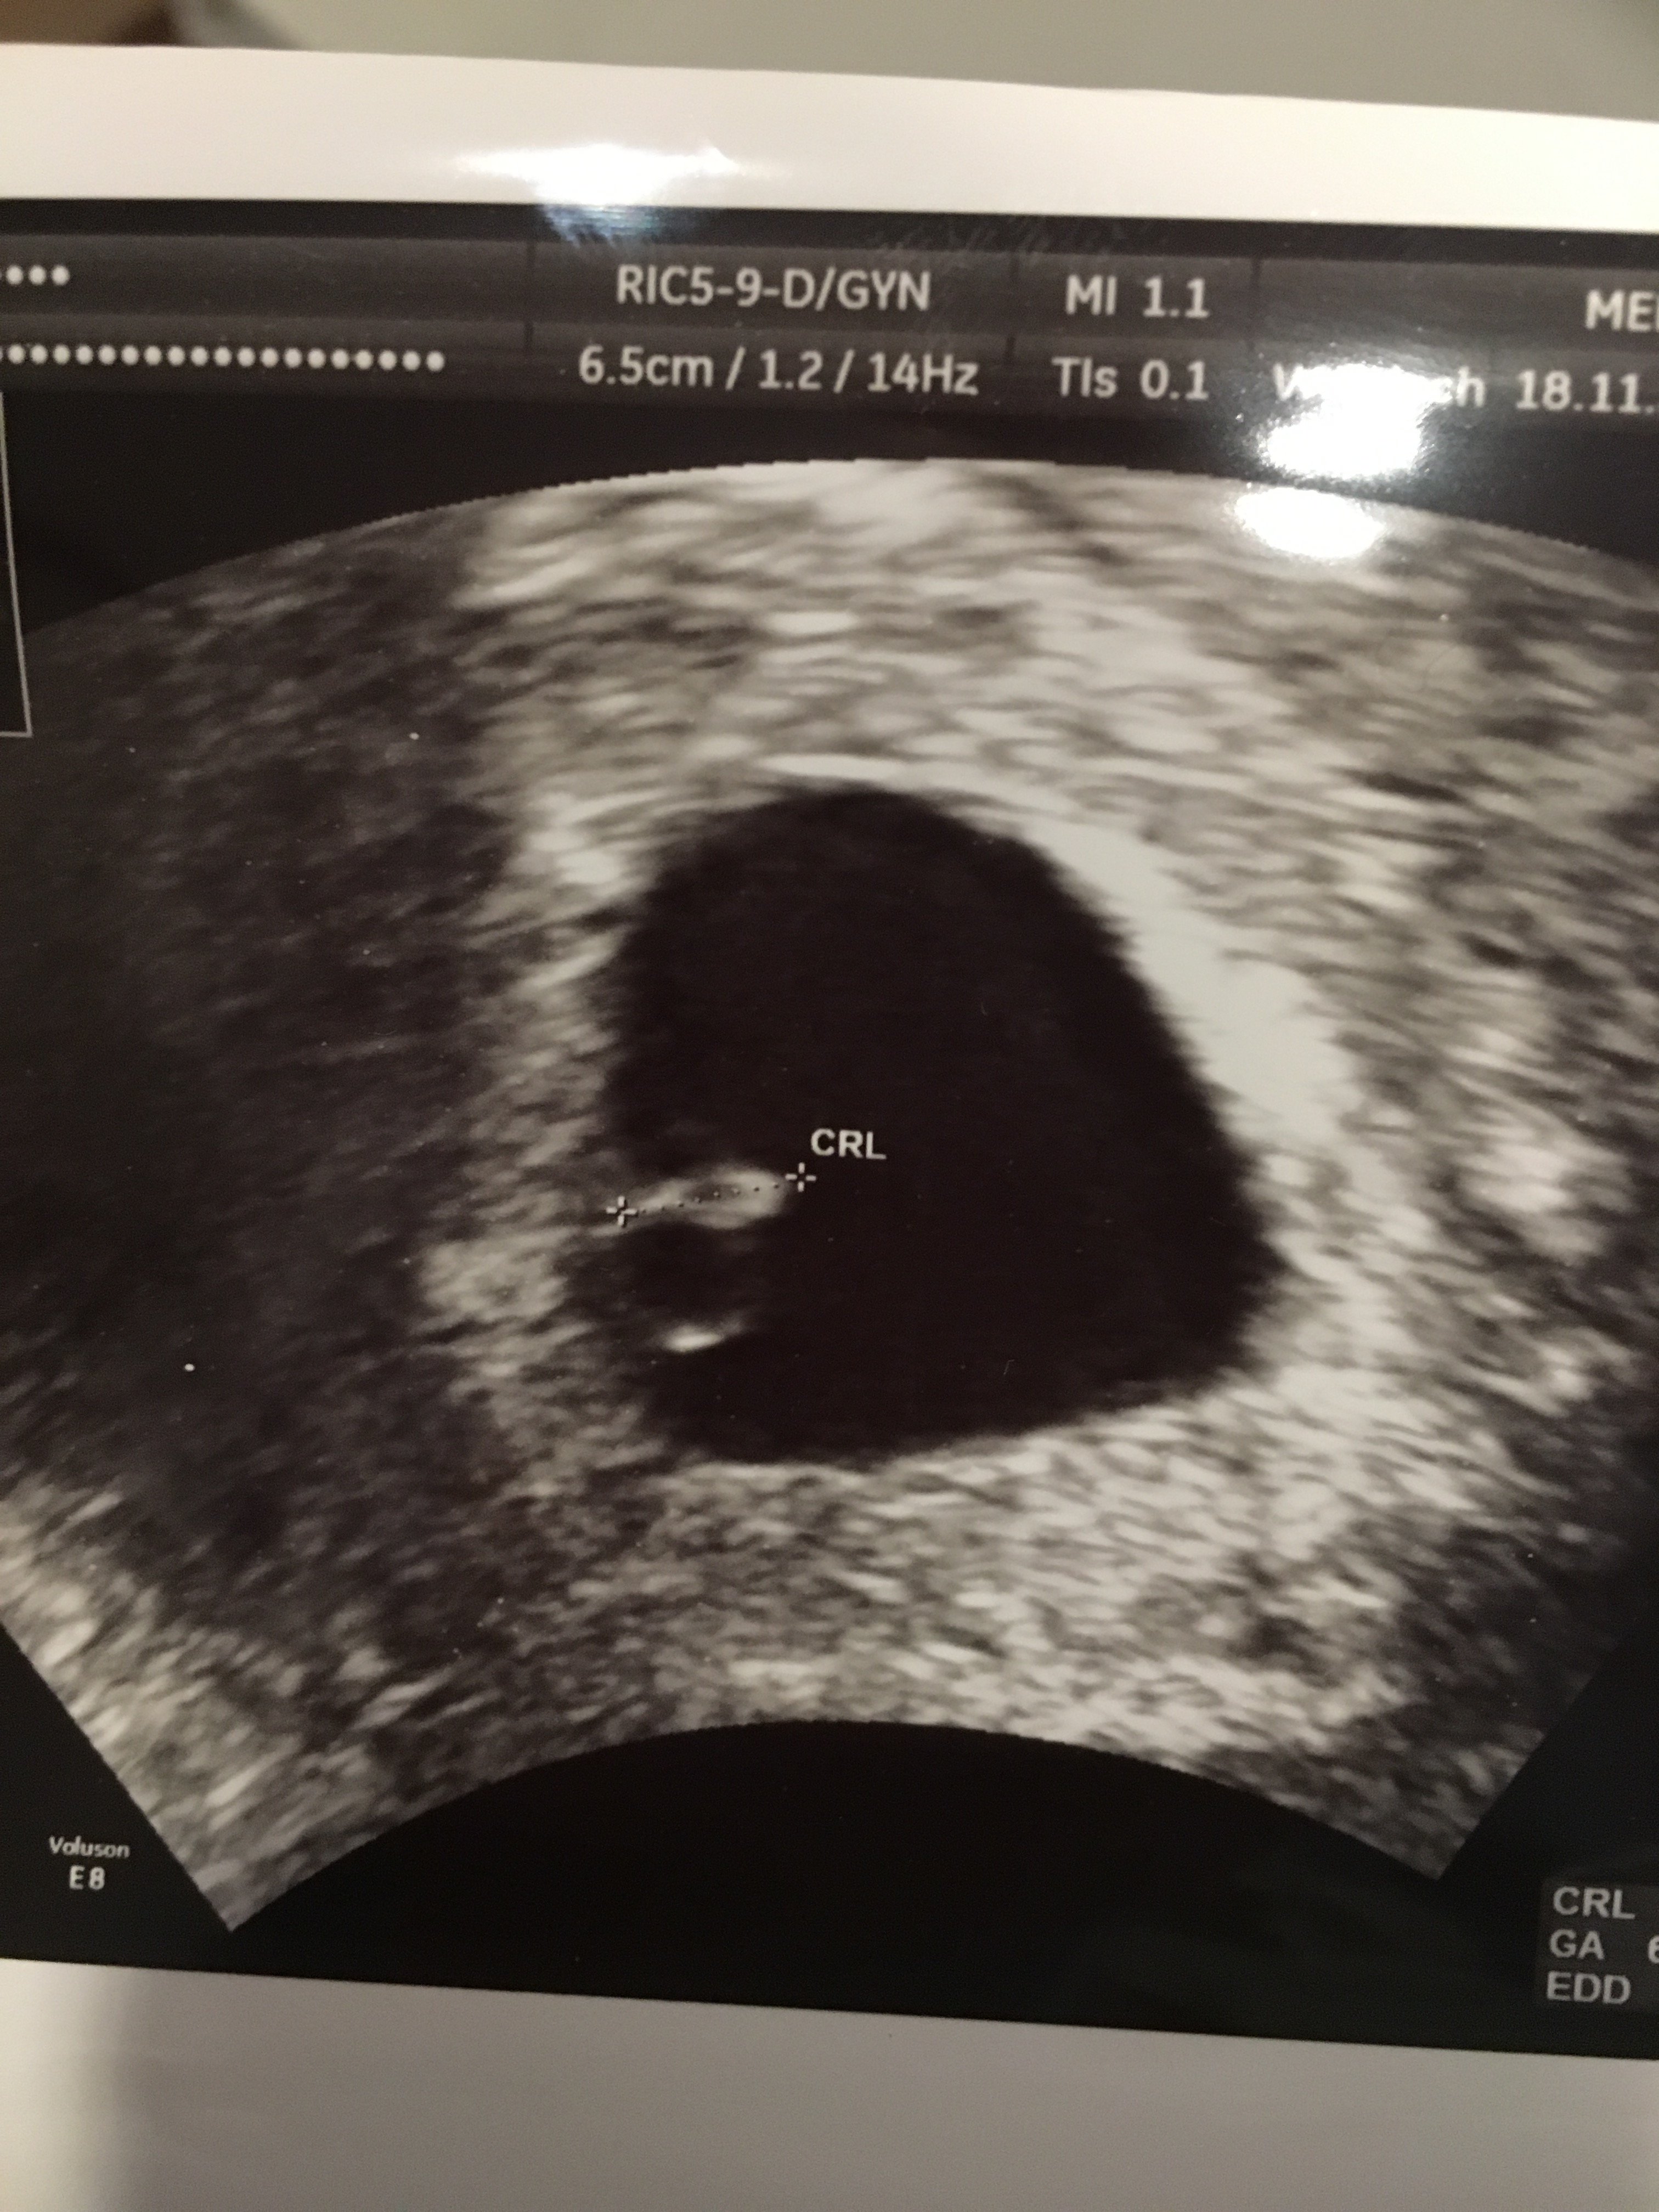

Gratuluję wszystkich usg! Szczęśliwie wszystko się układa i oby tak dalej, cieszę się że już każdy u siebie w domku a nie w szpitalu. Zazdroszczę Wam że już widzialyscie dzieciaczki, ja mam termin do lekarza na 27.11 dopiero